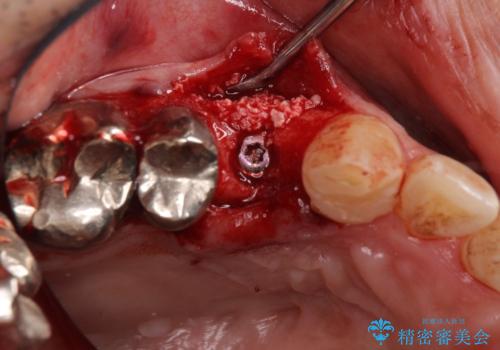

左上の奥歯は2本抜歯が必要であったため、治療期間中は右側に負担がかかり、頻繁に仮歯が壊れてしまいました。

左上に仮歯が装着されたからは咬み合わせが安定し、スムーズに治療を進めることができました。

- 外科手術のため、術後に痛みや腫れ、違和感を伴います